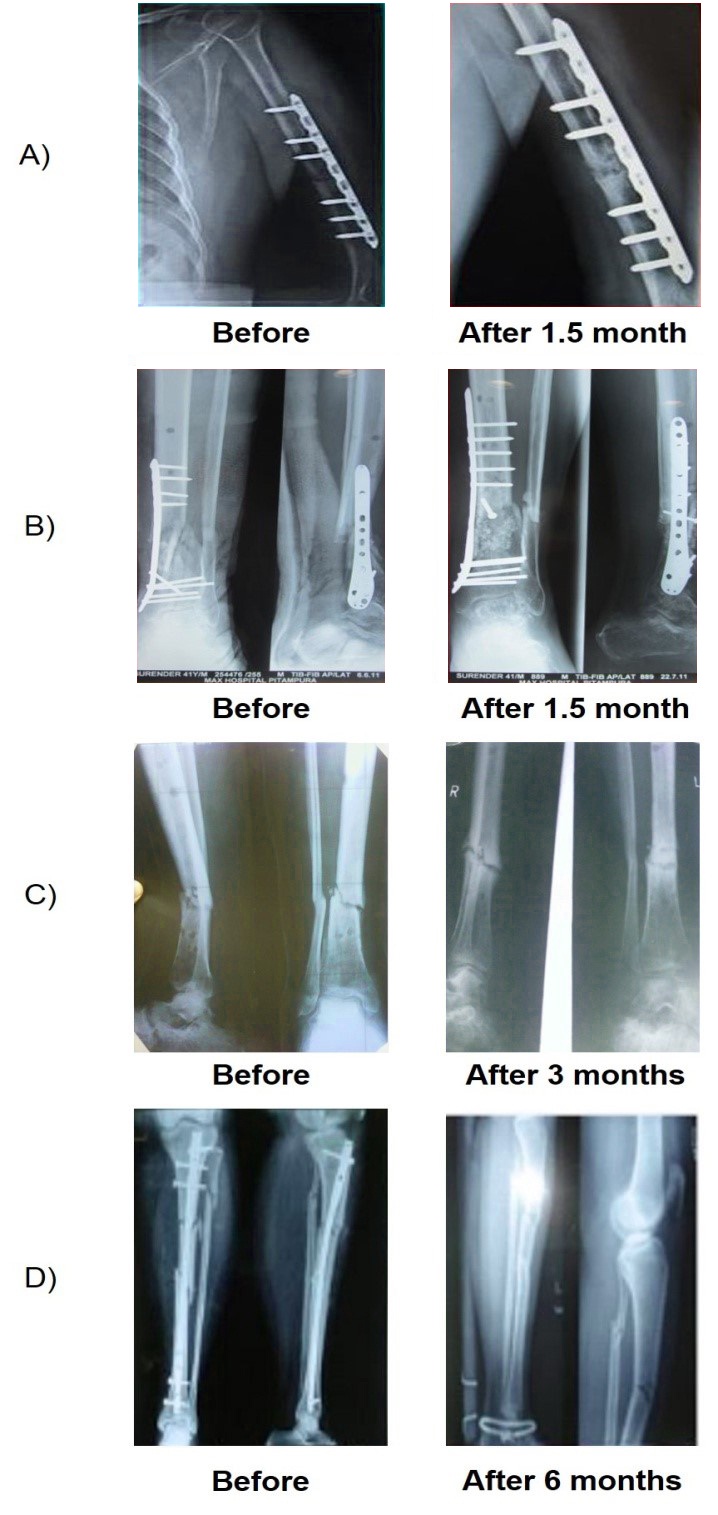

From www.orthohyd.com

FRACTURE / Bone Break / Fractured bone Max Superspecialty Ortho Clinic Fracture In Bone Marrow Or, it may be related to a health condition like osteoarthritis, a bone infection, a. Bme may be related to specific health conditions such as cancer,. Trauma can arise from an acute injury (acute fracture, bone marrow contusion) or be secondary to repetitive injury (fatigue and insufficiency fractures as well as stress reaction). A bone marrow edema — often referred. Fracture In Bone Marrow.

Enhancement of Atrophic NonUnion Fracture Healing Using Autologous Fracture In Bone Marrow Bme may be related to specific health conditions such as cancer,. The authors outline a systematic. Bone marrow edema is a buildup of fluid inside your bones. It can happen because of an injury such as a fracture. A bone bruise is thought to occur when there is a microscopic fracturing of the internal bone structure. Bone marrow lesions on. Fracture In Bone Marrow.